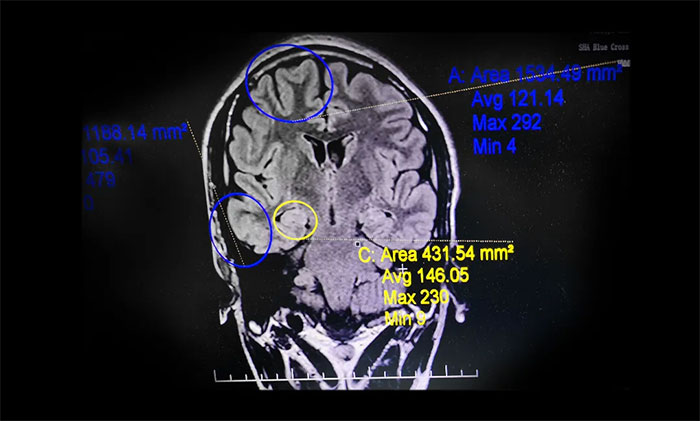

▲ 系列检查,明确患者致癫灶

小杨病情困扰一家人多年,父母要求手术治疗的意愿强烈。杨忠旭教授团队经过全面细致的检查和详细的术前评估,最终明确患者致癫灶,且手术指征明确,未见明显手术禁忌症。